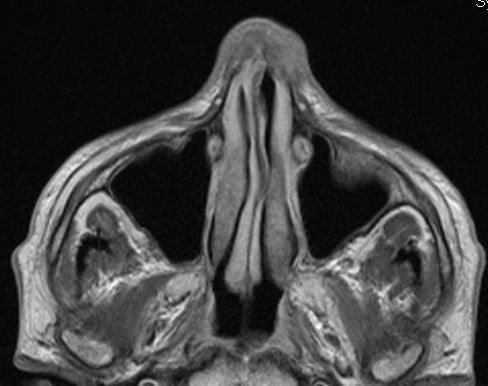

MRT: Plattenepithelkarzinom der rechten

Nasenhaupthöhle mit Infiltration der Nasenhaut![]() |